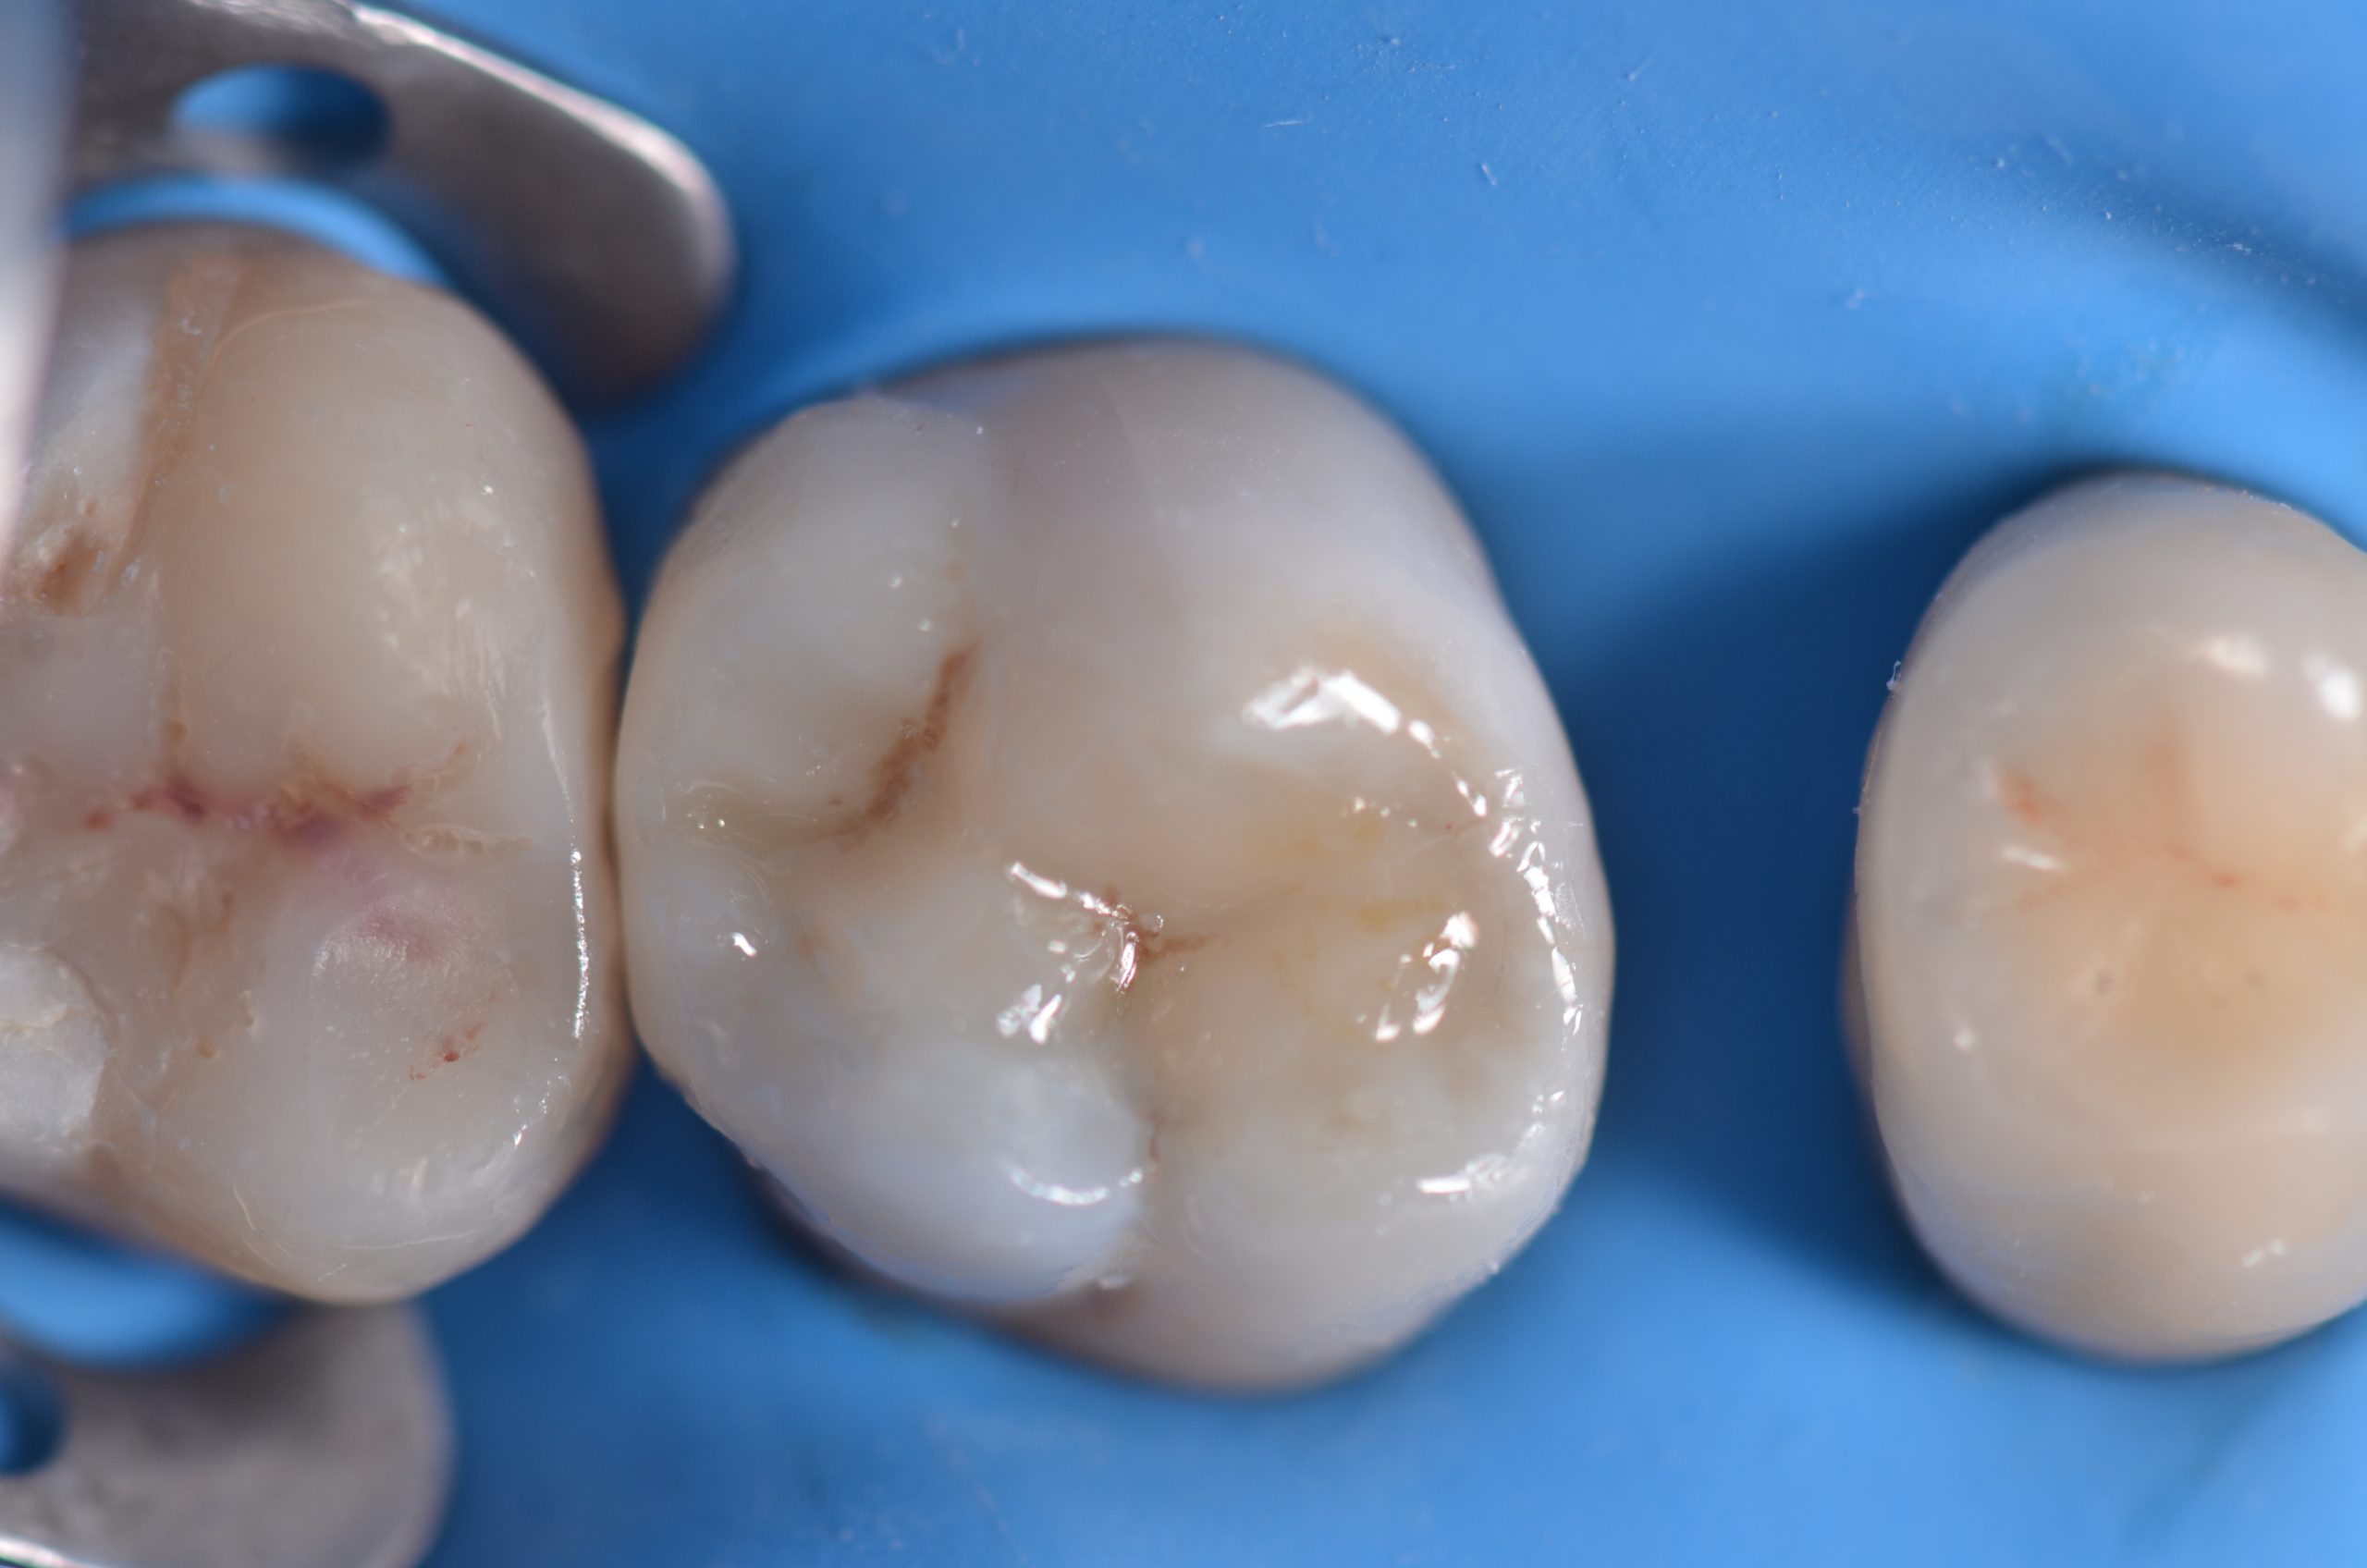

Una paziente di 44 anni si presenta alla nostra attenzione per la sostituzione di un vecchio restauro danneggiato. All’esame clinico si osserva la frattura della cuspide disto-palatina dell’elemento 1.6, associata a infiltrazione marginale di un restauro in composito incongruo. Le radiografie periapicali non evidenziano radiotrasparenze periapicali, ma mostrano possibili aree di demineralizzazione in zona marginale e all’interfaccia dente-restauro (1, 2, 3) (Figure 1-2).

Si esegue anestesia plessica con rinforzo intraligamentoso mediante articaina 1:100.000 sull’elemento 1.6. Successivamente si isola il campo con diga in gomma, utilizzando una clamp 27N sull’elemento 1.7 (Figura 3) con invaginazione del foglio a livello dei colletti.